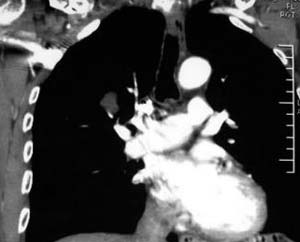

患者,男,58岁,煤矿职工,无症状,单位体检发现病变。

肺窗显示结节的后外边缘呈分叶状生长系生长过程受血管阻挡所致,出现较典型的“树凹”征,部分边缘见毛糙,不均匀强化,楼主未提供增强前后ct值,不好比较,倾向周围型ca。

右肺门上缘见类圆形节结影,密度尚均,边缘清楚,其内可见点状钙化影,周围支气管受压移位,病灶未见明显强化。考虑:1炎性假瘤  2 支持周围型肺ca (腺瘤)

右肺门上缘见类圆形节结影,密度尚均,边缘清楚,其内可见点状钙化影,周围支气管受压移位,病灶未见明显强化。考虑:良性病变——结核球可能性大,周围型肺癌待排。

病灶边缘光滑,似可见分叶征,未见明显毛刺。气管影轻度向右偏移。内可见点样钙化。邻近气道影通畅,考虑结核球可能。请楼主尽快公布结果

右肺门上缘见类圆形结节影,密度尚均,边缘清楚,其内可见点状钙化影,周围支气管受压移位,病灶未见明显强化。考虑:良性病变;首先考虑肺内错构瘤。次考虑肺内腺瘤。

病灶呈分叶型,边缘清晰,无毛刺,增强强化不明显,内见多发钙化,亦无卫星灶。多考虑良性病变。错构瘤可能性大。

病灶呈分叶型,边缘清晰,无毛刺,增强强化不明显,内见多发钙化,亦无卫星灶。多考虑良性病变。错构瘤可能性大或结核球。肺癌待排

动脉相上,右上肺动脉的尖段分支位于结节旁,结节对血管形成压迫而使到走行略改变,并没有很明确的包绕,也没有动脉期的供血,考虑还是偏向于良性可能大。当然最后的决定还是病检

病变边界清晰,对周围主要是外压性改变,未见血管包绕,边缘及中心见钙化,考虑良性病变,结核球可能